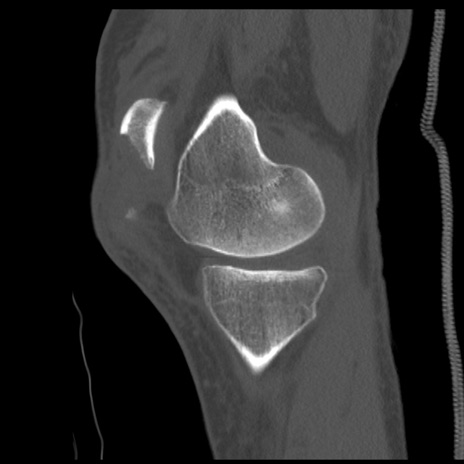

症例28 右膝関節CT(矢状断像)

右膝関節CT